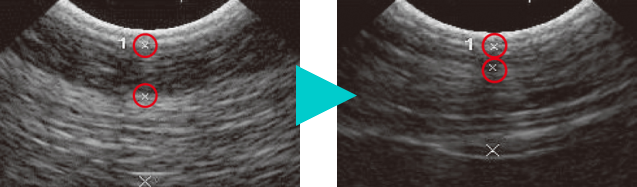

脂肪融解効果を証明する超音波画像

A:照射前

ヴァンキッシュ照射前は、7.6mmと測定された脂肪層の厚さ(上部1の○から○までの厚み)

B:照射後

ヴァンキッシュ照射後には、2.9mmに減ったことを証明する超音波画像